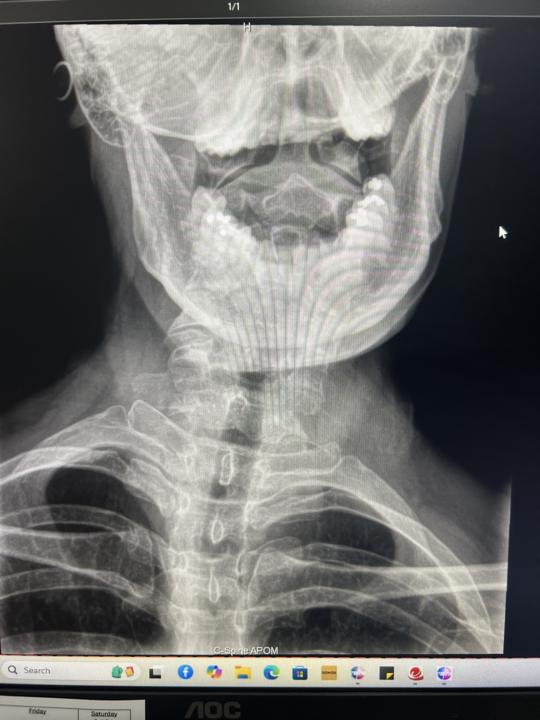

6yo with headaches and neck pain

6 yo with neck pain and spasm- getting frequent headaches and migraines Referred him to see a dentist due to the X-rays- any other recommendations